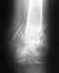

Глубокоуважаемые коллеги!Я являюсь врачом-неврологом,мне 29 лет, в 21 год мне был установлен эндопротез левого тазобедренного сустава по поводу коксартроза (б-нь Пертоса?). Эндопротез Mathys Medical CBC ножка бесцементная, RM чашка металл-металл, головка CoCrMo.

Я не занимаюсь серьезным спортом, нагрузки повседневные (езжу на машине) + иногда хожу в бассейн. Вопрос такой - каков срок службы такого эндопротеза? Какие перспективы в плане повторных операций, ревизий и т.п.Клинически жалоб нет, только немного больно бывает когда встаю после длительного сидения, или после того, как ногу на ногу ставишь сидя, держишь долго.После того, как встаю со стула мне требуется время "расходиться", я не смогу перенести всю массу тела на больную ногу, прихрамываю, после 25-30 шагов все в порядке. Rg делаю 1-2 раза в год, для контроля, и если очень много хожу, то болеть нога начинает, пару раз долго и сильно болела, вот и делал повторную рентгенографию. К этим всем особенностям я уже давно привык.

Когда, не знаем - наверное, когда будут проблемы. Ежегодный мониторинг рентгенограмм и клиники поможет Вам и Вашему врачу-ортопеду решить вопрос о

наступлении срока ревизии. Снимки пли-и-з. Ваша масса плии-из и много-много разных жалоб и критериев. Хабаровск. Доктор Рыков АГ.